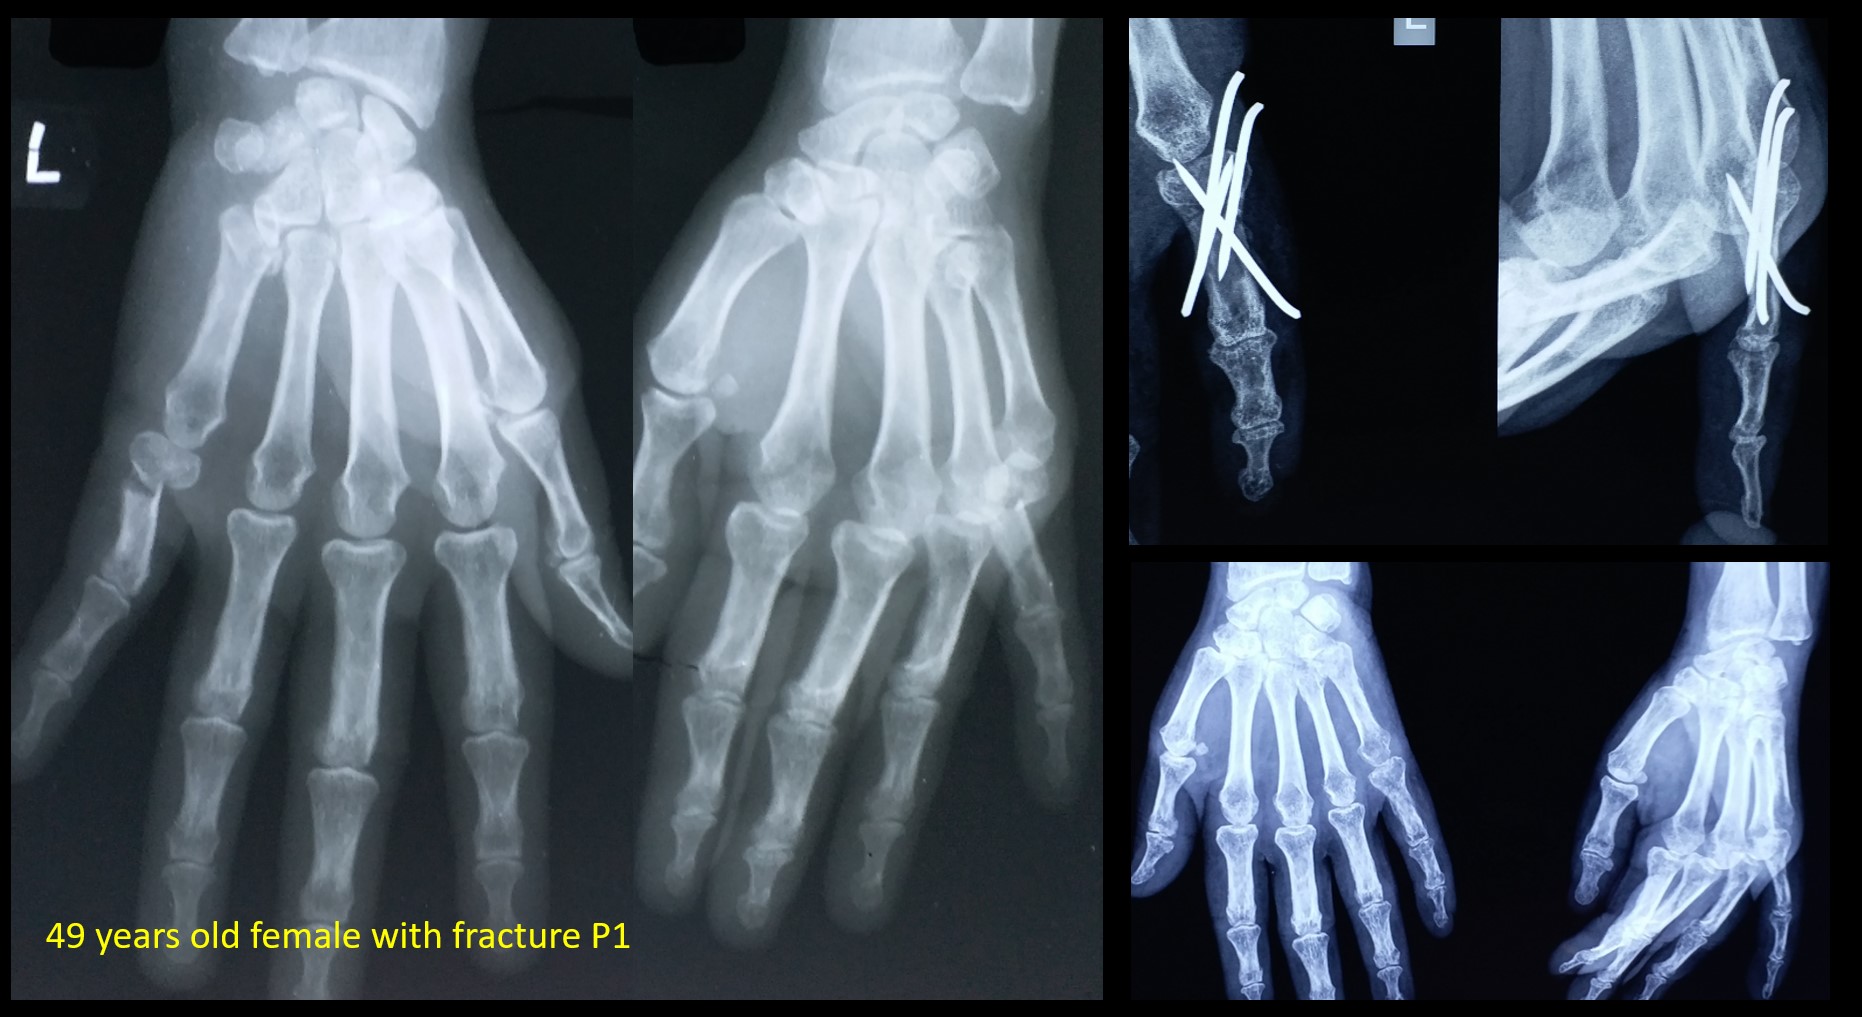

CRPP FRACTRUE PHALANX